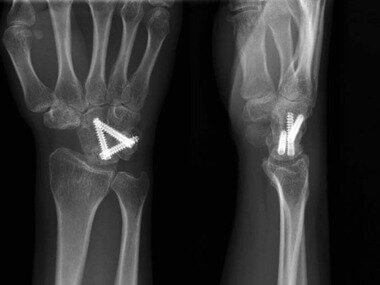

압박 금속나사를 이용한 사중관절 유합술© News1